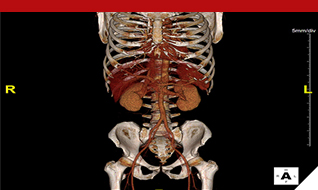

- 최신영상기술인 MRI와 CT, 핵의학에 대해 체계적으로 학습하며, 관련된 분야에 즉시 적용 가능하도록 교육을 실시합니다.

- 3차원영상처리 프로그램을 이용하여 영상을 만들어보고 영상해부학을 3차원으로 익히며, 미래의 IT 환경에 적응력을 높이고, 실무면접을 대비하는 교육을 실시합니다.